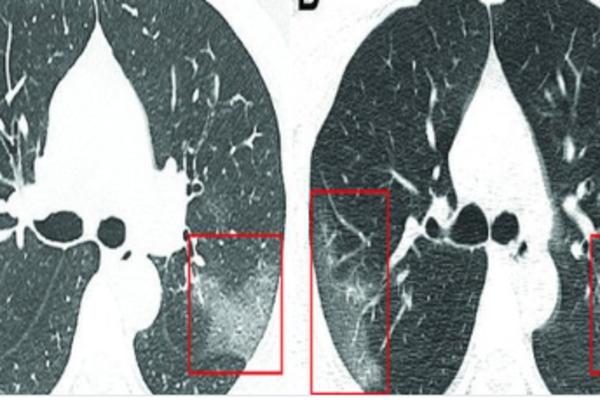

ŠOKANTAN SNIMAK PLUĆA ZARAŽENIH OD KORONAVIRUSA: Lekari uočili bele senke poput MLEČNOG STAKLA (FOTO)